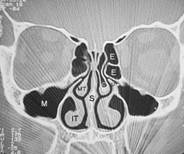

Da man sich als Laie schlecht vorstellen kann wo genau diese Nasenmuscheln in der Nase sitzen hier zusätzlich zu dem oberen Bild ein frontaler Querschnitt durch das Mittelgesicht:

Abb. 1   Abb. 2

Abb. 1: Hier relativ normale Verhältnisse. Die Nasenmuscheln lassen noch genügend Luft (schwarz) durch die Nasenhöhle strömen obwohl die Scheidewand leicht verkrümmt ist. Die Kennung IT zeigt wo sich die entsprechende zu verkleinernde Nasenmuschel befindet

Abb. 2: Auf der rechten Seite des Bildes sehen sie verdickte untere Nasenmuschel und seitlich daneben die Kieferhöhle (M). Die Nasenatmung ist hier einseitig stark eingeschränkt. Die dünnen schwarzen Linien stellen die noch verfügbare Nasenatmung links dar!

Erklärung: Schwarz: Luft, Graustufen: Weichteile, Weiß: Knochen, IT: untere Nasenmuschel, M: Kieferhöhle, S: Nasenscheidewand